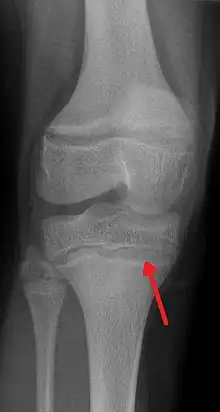

One of the clinical signs of rickets that doctors look for is cupping and fraying at the metaphyses when seen on X-ray.